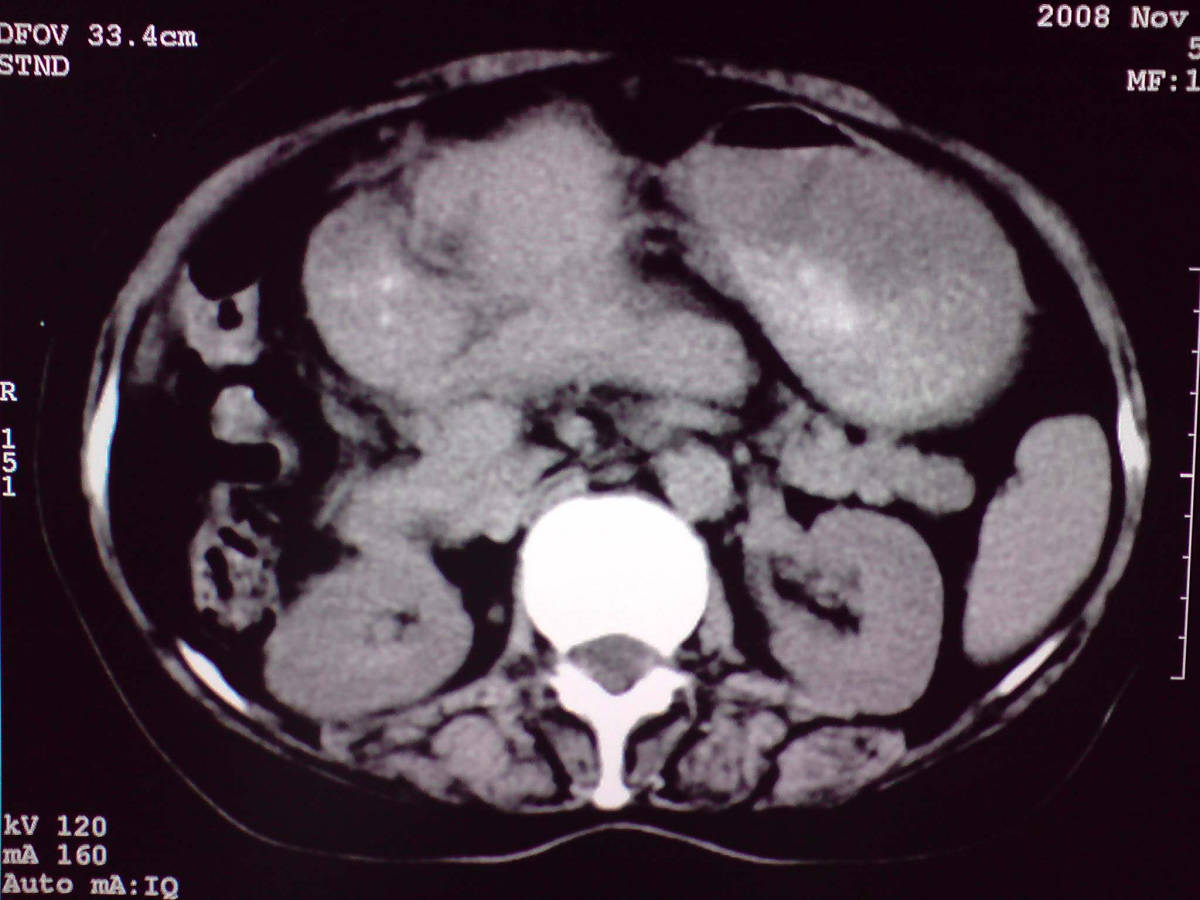

女性,60岁,上腹不适、自感胃部疼痛

小网膜区见类圆形软组织密度肿块,密度不均,内见不规则低密度区,与肝左叶分界模糊,肝脏体积缩小,密度不均匀,边缘呈波浪状,尾状叶明显增大,脾脏下缘明显超出肝脏下缘。

意见:肝硬化并外生性肝癌,建议增强扫描。

肝脏比例失调,形态失常,外缘呈波浪状,腹腔内肿块内见低密度区并与肝脏界限欠清

考虑外生性肝癌,左肺下叶占位,肝硬化

有肝硬化背景,肝胃间隙见不规则形,且密度不均匀的占位性病变,与肝左叶分界不清,首先考虑外生性肝癌可能性大,不排外肝胃间隙恶性占位肝脏受侵可能性。左肺下叶结节影,其内见空泡征,边缘见毛刺,从一元化的角度首先考虑转移。

1 肝脏各叶比例失调,形态失常,外缘呈波浪状。右叶萎缩,左叶 尾叶增大。2 腹腔内软组织密度肿块,低于肝实质密度,内见低密度区,并与肝脏界限欠清。腹膜后见肿大淋巴结,并与腹腔肿块关系密切。3 左肺下叶肿块,见边缘毛刺征及胸膜凹陷征,并与近肺门侧见异常血管相连。

综合考虑:左下肺周围性肺癌伴腹腔 腹膜后淋巴结转移!另:肝硬化!

1肝胃韧带区域一肿块,肿块上缘与肝左叶相连。肝硬化。考虑肝外生型肝癌可能性大,不除外间质瘤。2左肺下叶背段一结节,有偏心性空洞,长毛刺,其周有多发小结节。考虑结核可能性大。

感谢大家的讨论,今天拿到病理结果是肝细胞癌